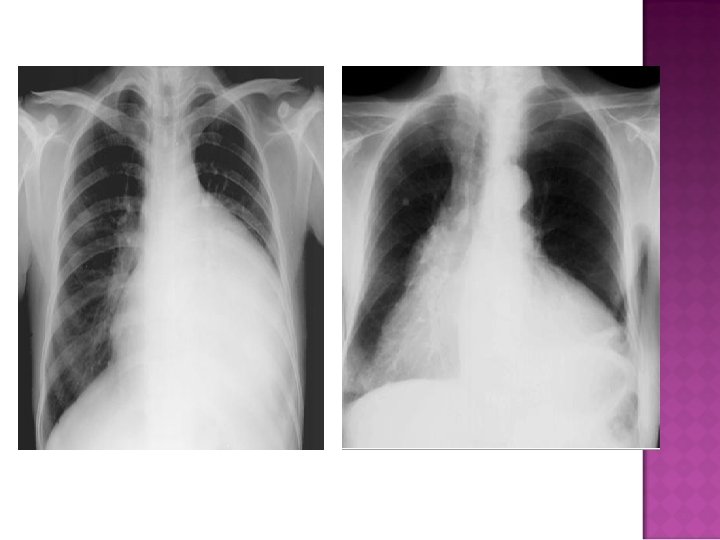

Cardiomegaly due to a massive pericardial effusion. At least 200 m. L of pericardial fluid must accumulate before the cardiac silhouette enlarges.

Sudden inc in size of cardiac silhouette w/o specific chamber enlargement Effacement of the normal cardiac borders Development of a “flask” or “H 2 O-bottle” shaped heart

May have (+) fat pad sign Separation of mediastinal / retrosternal fat and epicardial fat by > 2 mm

Normal in patients with acute pericarditis unless pericardial effusion is present Enlarged cardiac silhouette Requires 200 cc of fluid